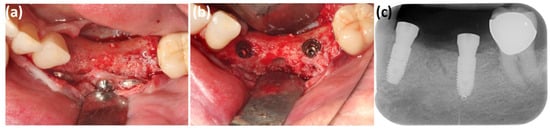

Clinical Outcomes of Bovine Bone Xenografts Following Sequestrectomy in Advanced Medication-Related Osteonecrosis of the Jaw

Background/Objectives: Bisphosphonates, a class of drugs that are widely used in the treatment of neoplastic diseases, can lead to the development of medication-related osteonecrosis of the jaw (MRONJ). This condition is challenging to manage due to the high incidence of postoperative complications: superinfections, local wound dehiscence, or fractures in pathological bone. The aim of this study is to evaluate the therapeutic role of bovine-derived xenografts in the management of MRONJ. Methods: This retrospective observational study evaluates the clinical outcomes of patients with confirmed stage II or III MRONJ, after surgical treatment with Bio-Oss application. All patients had received zoledronic acid therapy, which was discontinued for a minimum of four months prior to surgical intervention. The surgical protocol included local debridement, sequestrectomy, and grafting of the residual defect with a bone substitute, followed by periodic clinical evaluations and monitoring of local healing with a follow-up period of up to one year. Results: Of the total number of patients treated according to this surgical protocol, 85.71% achieved favorable healing without complications at 8 weeks. Cases with poor local healing results were more likely to have prolonged zoledronic acid administration. Conclusions: Within the limits of this retrospective observational study, the use of bovine-derived xenografts following sequestrectomy in stage II–III MRONJ was associated with satisfactory local healing in several cases. However, considering the limited sample size and lack of a comparator group, these findings should be interpreted cautiously. To better understand the connection between the length of antiresorptive therapy, surgical management techniques, and postoperative outcomes, more prospective, multicenter trials with bigger patient cohorts are needed. Full article

Figure 1